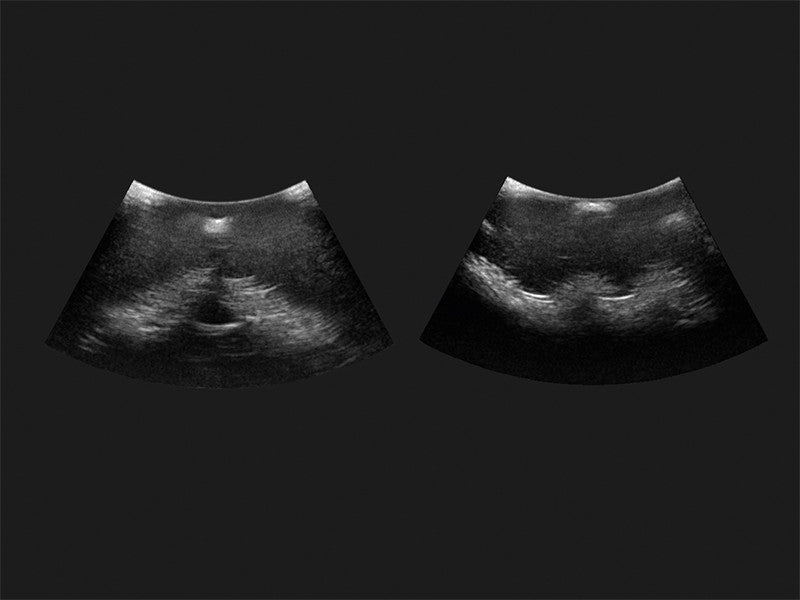

Our range of epidural injection trainers includes detailed anatomical models that replicate the lumbar and thoracic spine, providing a hands-on learning experience for anaesthetists, medical students, and pain management specialists. These advanced simulators allow users to practise needle placement, identify key anatomical landmarks, and develop proficiency in administering epidural and spinal anaesthesia with confidence. Ideal for medical schools, hospitals, and professional training programmes, these epidural trainers support skill development in regional anaesthesia, labour pain management, and spinal procedures. With lifelike materials that simulate real patient responses, our models offer a realistic and immersive training experience.